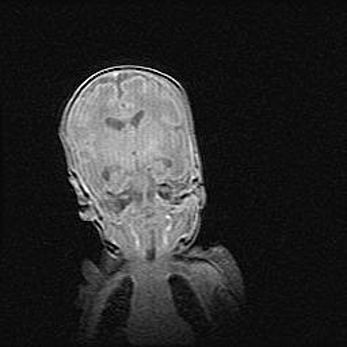

Наружная гидроцефалия с возможной атрофией височных областей.

Возраст: 28 дней

Вес: 3670 г

Пол: мужской

Окружность головы: 38 см

Срок гестации: 40 недель

Гидроцефалия головного мозга у новорожденных – это заболевание, которое характеризуется скоплением избыточного количества спинномозговой жидкости в желудочковой системе головного мозга в результате затруднения её перемещения от места выработки к месту поглощения в кровеносную систему или вследствие нарушения абсорбции. При открытой наружной форме гидроцефалии у новорожденных расширяются и переполняются субарахноидные пространства.

При нормотензивных  формах,  которые,  как  правило,  являются  следствием  перенесенных ишемических  повреждений  паренхимы  мозга,  возможно  сочетание микроцефалии  с нормотензивной гидроцефалией. В основе данных изменений лежит атрофия больших полушарий с преимущественной  локализацией  в  лобно-височных  областях.